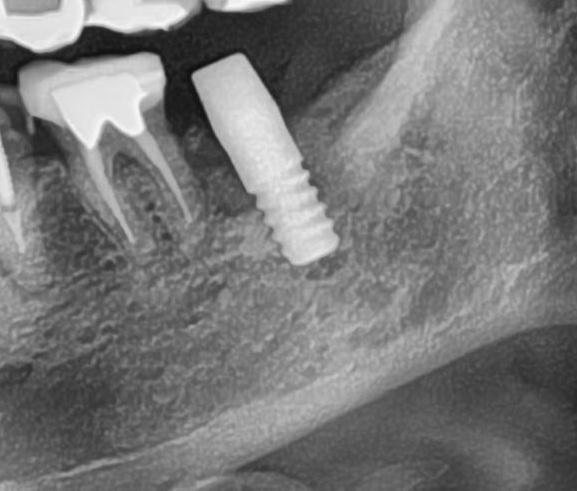

開けた穴に、専用道具を使ってネジを締めるように長さ2センチ程のインプラントを骨に埋め込んでいきます。

しっかりとインプラント埋め込まれた後は、動揺がないか、噛んだ時に当たらないかなどを確認して、最後にパノラマ写真を撮影して今回のオペは終了となりました。